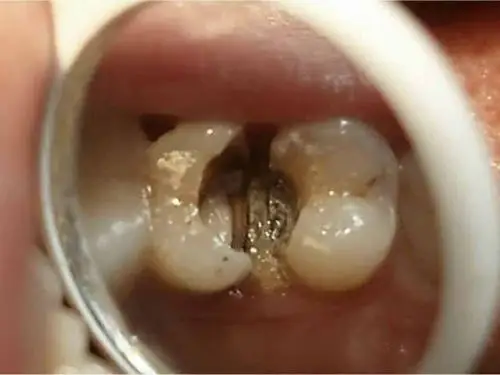

根尖周炎

最近几例根尖阴影比较大的根尖周炎

从而导致脓肿,也就是牙根顶端的局部感染,诱发牙髓炎和根尖周炎

急性根尖周炎

急性根尖周炎的是能够自我察觉的,表现为牙龈肿胀,咬合痛或自发性疼痛

对于急性根尖周炎患者而言,可以口服消炎药止疼,然后去医院做根管